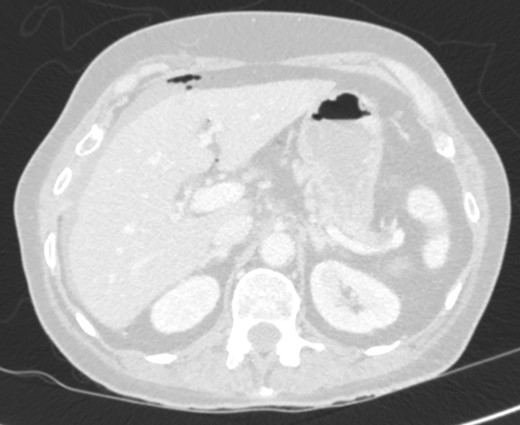

On examination, she was febrile. Her abdomen was generally tender. Bowel sounds were present and up to that time her stoma was working. Her perineal hernia was red and tender. Her initial CXR (Fig. 1) did reveal a sliver of gas underneath her right hemidiaphragm and in keeping with her abdominal findings she progressed to further imaging. CT abdomen pelvis with contrast showed pneumoperitoneum (Fig. 2) with ‘a tiny pocket of air is also seen adjacent to a loop of bowel in the pelvis posterior to the bladder’. ‘Exact site of perforation has not been demonstrated but could possibly be in the bowel loops in the perineum’ (Figs 3 and 4).

CT showing small bowel loops in pelvis with perineal hernia and free fluid.